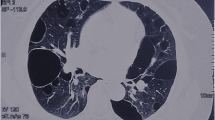

A total of 39 patients (37 Females, 2 Males) from 31 distinct families were diagnosed with BHDS by genetic testing (Table 1). The average age at diagnosis was 45.8 years (median = 48 y, range: 15–72 y, with one case unknown). Based on all information available, 85.7% (24/28) BHDS patients have a family history of lung cysts and/or spontaneous pneumothorax, and 2 (7.1%, 2/28) patients have a family history of renal tumor. In our cohort, 3 patients failed to follow-up, and all the rest 36 (100%, 36/36) patients have lung cysts (Fig. 1a), and 21 (58.3%, 21/36) have a history of pneumothorax. Seventeen (47.2%, 17/36) patients got cutaneous lesions (Fig. 1b) with multiple white or skin colored papules on the face, neck and/or feet. Renal impairment was observed in 9 (30%, 9/30) patients, including 8 with unilateral or bilateral renal cysts (Fig. 1c) and 1 with renal hamartoma. No malignant renal tumor was found in this cohort.

Respiratory system was the most frequently affected system in these BHDS patient as we reported before [7], with frequencies of almost 100 and 58.3% for lung cysts and pneumothorax respectively. Similarly, a recent epidemiologic study of Japanese BHDS patients reported that all except one family had lung cysts and 73.7% presented with episodes of pneumothorax in their cohort [6]. By comparison, lower prevalence of lung cysts (70–85%) was reported in Caucasian BHDS patients and only about one-third patients reported a history of spontaneous pneumothorax [4, 5, 17, 18]. Thus, it seems that pulmonary manifestations are more frequently observed in Chinese BHDS patients. What is worth mentioning is that the Caucasian patients from literature were all recruited through referrals from department of dermatology or urology. While, most patients in this study came to our clinic because of cysts in the lung. So, selection bias should be responsible, at least partially, for the different frequencies of pulmonary manifestations between Chinese and Caucasian BHDS.

There are some limitations in our study. Firstly, data missing is a major problem, especially for renal and cutaneous examinations. Data about kidney examination in 9/39 patients are not available, which make it difficult to correctly define the prevalence of renal impairments. Because skin lesions like fibrofolliculomas are generally neither painful nor pruritic, most patients were reluctant to accept invasive biopsy. Thus, only one patient was diagnosed with typical skin lesions by histological confirmation. Secondly, most of the patients were recruited from a single center, Department of Pulmonary and Critical Care Medicine, PUMCH, which is a referral center for rare pulmonary diseases in China. Patient were likely to be referred to our hospital when they have lung cysts on radiological scans. So, the finding of 100% lung cysts in this cohort should be used carefully, due to obvious selection bias. However, in these genetically confirmed BHDS patients, cutaneous involvements and renal tumors were much less frequently detected than in those reported in Caucasians. Given that skin, pulmonary, and renal symptoms appear independently in BHDS, our data even incomplete still support that Chinese BHDS patients have fewer skin lesions and kidney tumors.

From February 2017 to February 2019, patients with unexplained multiple cysts and/or spontaneous pneumothorax visiting Peking Union Medical College Hospital (PUMCH) were screened for suspected BHDS. A total of 47 patients from 39 unrelated families were enrolled in this study and received genetic testing following the inclusion criteria proposed by the European BHD Consortium [23]. More concretely, patients with the following conditions were highly suspected of having BHDS: (1) having multiple lung cysts, especially bilaterally and basally located, or spontaneous pneumothorax with no apparent cause; (2) having a family history of cystic lung disease, pneumothorax or familial kidney cancer; (3) with any combination of unexplained lung cysts/pneumothorax, skin lesions like fibrofolliculomas or trichodiscomas confirmed by dermatologists, and nephropathy. Chest CT were applied to scan for lung impairments. Other diffuse cystic lung diseases, like lymphagioleiomyomatosis, light chain deposition disease, amyloidosis, infectious pneumocystis, tuberous sclerosis, lymphoid interstitial pneumonia and pulmonary Langerhans cell histiocytosis were excluded by high-resolution computed tomography. Skin examination was carried out in most patients and skin lesions were diagnosed by an experienced dermatologist. Renal involvements were detected by renal ultrasonography, abdominal CT scans and/or MRI. The study was approved by the Institutional Review Board committee at PUMCH.